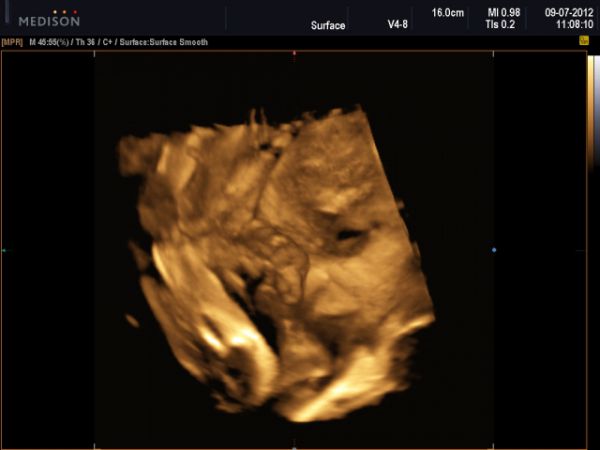

Včera jsme s naší princeznou absolvovali 3D UZ, sice trochu později,ale přece jen bylo něco málo vidět, tak mi ta naše dračice dala krásný dárek k narozeninám :-)